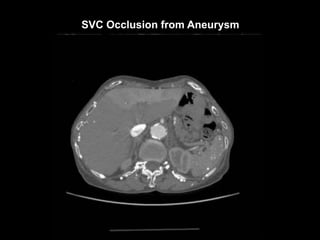

SVC Occlusion from Aneurysm

90cc contrast, 60 sec diagnostic delay.

Imaging range: angle of mandible to lesser trochanters.

LT IJV